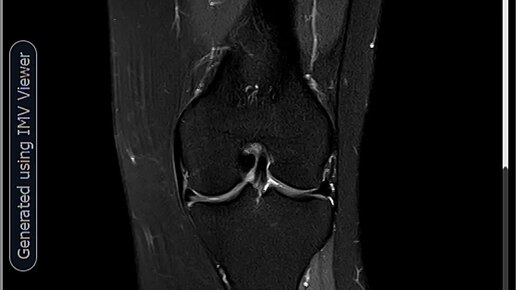

МРТ-Повреждение мениска коленного сустава Stoller 3a